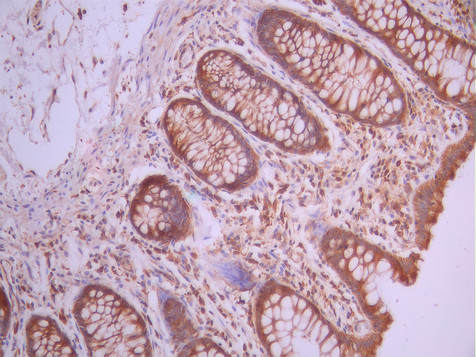

IHC image of CSB-RA794271A0HU diluted at 1:100 and staining in paraffin-embedded human small intestine tissue performed on a Leica BondTM system. After dewaxing and hydration, antigen retrieval was mediated by high pressure in a citrate buffer (pH 6.0). Section was blocked with 10% normal goat serum 30min at RT. Then primary antibody (1% BSA) was incubated at 4°C overnight. The primary is detected by a Goat anti-rabbit polymer IgG labeled by HRP and visualized using 0.05% DAB.

IHC image of CSB-RA794271A0HU diluted at 1:100 and staining in paraffin-embedded human colorectal cancer performed on a Leica BondTM system. After dewaxing and hydration, antigen retrieval was mediated by high pressure in a citrate buffer (pH 6.0). Section was blocked with 10% normal goat serum 30min at RT. Then primary antibody (1% BSA) was incubated at 4°C overnight. The primary is detected by a Goat anti-rabbit polymer IgG labeled by HRP and visualized using 0.05% DAB.